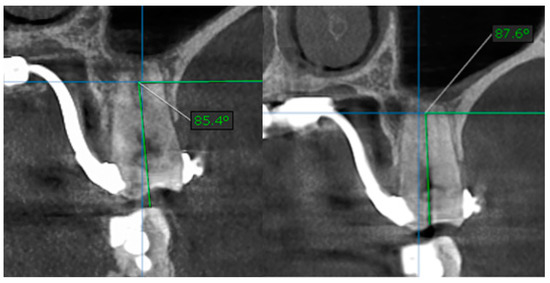

| D’Agnostino & Pearson Omnibus Normality Test | 1st Molar Tilt after Treatment | 1st Molar Tilt before Treatment |

|---|---|---|

| Number of vales | 40 | 40 |

| Minimum | 85.60 | 84.00 |

| 25% Percentile | 87.60 | 85.23 |

| Median | 88.00 | 85.65 |

| 75% Percentile | 88.65 | 86.70 |

| Maximum | 89.30 | 87.90 |

| Mean | 87.88 | 85.87 |

| Std. Deviation | 1.001 | 1.057 |

| Std. Error of Mean | 0.2238 | 0.2363 |

| Lower 95 % CI of mean | 87.41 | 85.38 |

| Upper 95 % CI of mean | 88.34 | 86.36 |

| Table Analyzed | Data 1 |

|---|---|

| Column B | 1st Molar tilt before treatment |

| Vs. | Vs. |

| Column A | 1st Molat tilt after treatment |

| Paired t test | |

| p value | < 0.0001 |

| p value summary | |

| Significantly different? (p < 0.05) | yes |

| One- or two-tailed P value | Two-tailed |

| t, df | t = 12.33 df = 19 |

| Number of pairs | 40 |

| How big is the difference | −2.005 |

| SD of differences | 0.7273 |

| SEM of differences | 0.1626 |

| 95% confidence interval | −2.345 to −1.665 |

| R square | 0.8889 |